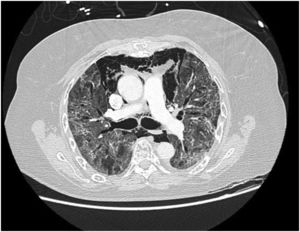

In our study, CT was used to identify and confirm spontaneous PM and PM relative to mechanical ventilation. The scannographic signs of PM relied on the anatomical region occupied by the air as it exits the mediastinum.20 (Figs 1, 2).

Pneumomediastinum (PM) is a condition where the air is present in the mediastinum. Free air leaks from ruptured alveoli, dissecting along the bronchovascular sheaths towards the mediastinum. PM, as seen on chest CT, elevates the mediastinal pleura and can extend into the neck or chest wall.14 One of the first signs that simulate a pneumomediastinum is the Mach band effect. This optical effect at the margin between areas of faintly different density15 can mimic various other pathologies (pneumopericardium, fracture), and makes it possible to suspect PM in COVID-19 patients. Non-traumatic PM is a rare complication of COVID-19 pneumonia.16 Its development in COVID-19 infection is also considered a possible indicator of disease worsening, which may be or not be associated with invasive ventilatory support. Spontaneous PM seemed to be a frequent complication of severe acute respiratory syndrome (SARS).17 In 2004, a high peak LDH level of 863 IU/L had been correlated with spontaneous PM in SARS patients, likely due to significant remodeling of the lung tissue causing leakage and vessel wall dissection.17 Most patients with PM had lung involvement higher than 50% at the moment of the diagnosis,18 corroborating the increased risk of rupture and PM development. This study aimed to evaluate the association between baseline serum LDH levels and COVID19 lung necrosis outcome based on the extent of lobar involvement and PM development.